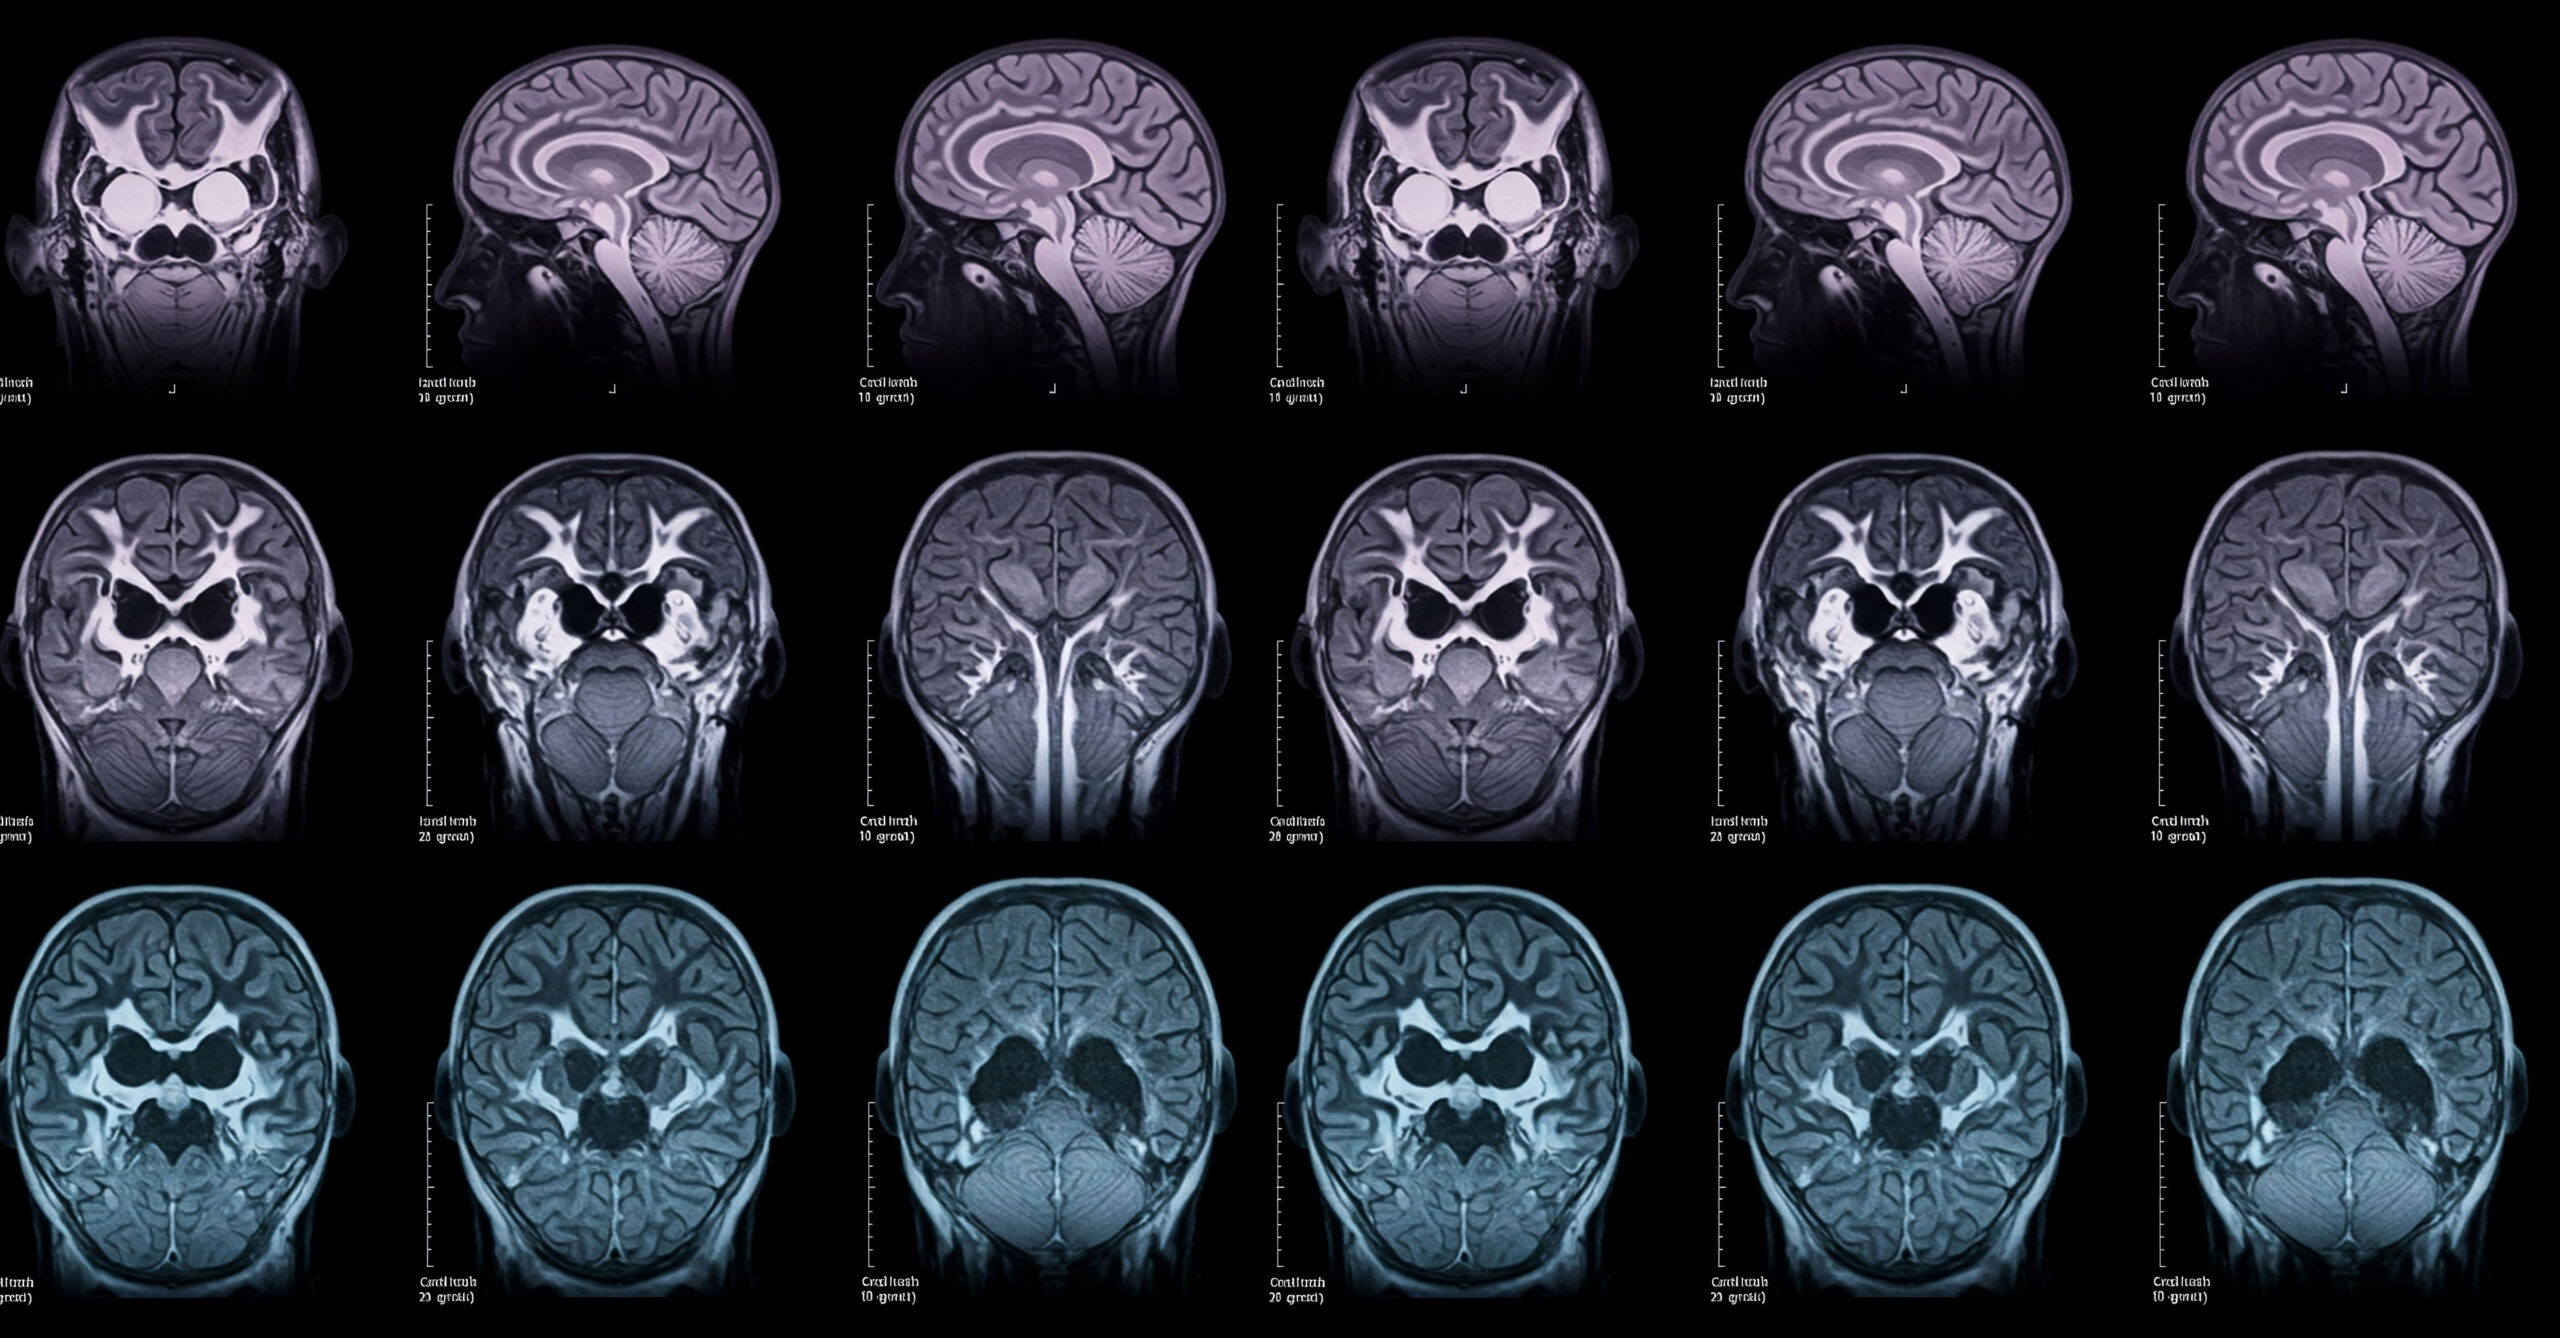

Neurology

Your generosity is driving breakthroughs in neurological care—enabling us to deliver earlier diagnoses, more precise treatments, and recovery-focused support that helps patients reclaim their lives and build lasting resilience.